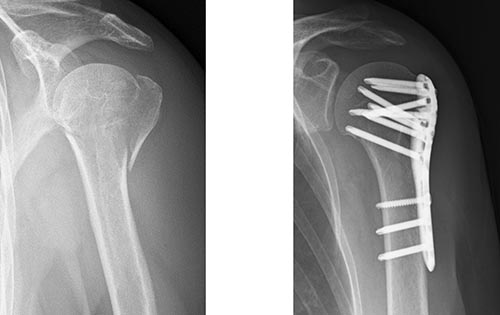

手術方法は、骨接合術は髄内釘固定法(図3)やロッキングプレート固定法(図4)が行われます。脱臼骨折の場合には、人工骨頭置換術が行われる場合もあります(図5)。近年リバース型人工肩関節置換術も用いられるようになり、臨床成績が安定しています(図6)。

図4 ロッキングプレート固定法